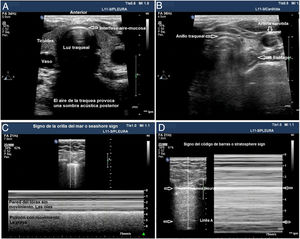

La ecografía traqueal ha mostrado tener el mismo valor que la capnografía para la exclusión de la intubación esofágica17. Para ello, es necesario utilizar una sonda lineal o convex y adquirir un plano transversal en la región anterior del cuello, en la línea media, encima de la escotadura esternal. En este plano, la tráquea se identifica como una línea hiperecogénica con forma de U invertida, generada por la interfase mucosa-vía aérea, y un artefacto posterior en cola de cometa (fig. 1A). La intubación correcta de la tráquea no produce cambios en la imagen descrita, dado que no se genera una nueva interfase entre la vía aérea del paciente y el TOT (ambas contienen aire) y, porque además, el TOT se encuentra detrás del artefacto generado por la tráquea (lo que limitaría su visualización). La intubación inadvertida del esófago se identifica ecográficamente porque produce una nueva interfase entre la mucosa esofágica y el aire contenido en el interior del TOT, que da lugar a un segundo artefacto en cola de cometa que nace a un nivel más profundo que la tráquea, y lateral a ésta (fig. 1B). La principal ventaja de esta exploración es que no precisa iniciar la ventilación para detectar la posición incorrecta del TOT, evitando la posibilidad de aspiración de contenido gástrico; las limitaciones son la imposibilidad para visualizar el TOT de forma directa en el interior de la vía aérea y las posibles alteraciones anatómicas que presente el paciente.

Utilidad de la ecografía traqueal y pleural para la comprobación de la IOT. A) Imagen de ecografía traqueal donde se visualiza la tráquea con su sombra acústica posterior y rodeada por la tiroides. B) Imagen de ecografía traqueal con el trasductor desplazado hacia la zona izquierda del cuello, la flecha señala cómo identificar el esófago. C) Imagen de ecografía pleural con patrón de aireación normal que indica que el pulmón está insuflado. D) Imagen de ecografía pleural con signo de código de barras que indica que el pulmón no está insuflado, posible intubación selectiva contralateral.

La ecografía pleural proporciona información anatómica directa sobre la expansión pulmonar y la entrada de aire en los pulmones18. Puede sustituir a la auscultación y a la radiografía de tórax como métodos para excluir la intubación bronquial selectiva inadvertida (IBSI). Para ello, es necesario utilizar una sonda lineal o convex y examinar, al menos, los puntos superior e inferior del protocolo BLUE en ambos hemitórax19. En estos planos, en ecografía 2D, la pleura se identifica como una línea hiperecogénica horizontal, que presenta un movimiento generado por el deslizamiento de la superficie de la pleura parietal sobre la visceral con los movimientos respiratorios, denominado lung sliding o signo del deslizamiento pulmonar20. En modo M se puede registrar también de forma estática cortando la línea pleural, lo que produce una imagen denominada seashore sign o signo de la orilla de la playa. La presencia de ambos signos en cada hemitórax es indicativa de insuflación bipulmonar (fig. 1C). La IBSI tiene como consecuencia la ausencia de aireación del pulmón contralateral, que se detecta mediante la ausencia de lung sliding, y un patrón en «código de barras» o signo estratosfera en modo M (fig. 1D). La transformación de un patrón en código de barras unilateral en un patrón de deslizamiento pulmonar normal, asociado a la retirada parcial del TOT, confirma que la posición inicial del tubo correspondía a una IBSI del pulmón contralateral (Algoritmo 1). Las principales ventajas de esta exploración son la posibilidad de demostrar aireación pulmonar sin utilizar fonendoscopio e inmediatez frente a la radiografía de tórax (Rx), la principal limitación deriva de la existencia de diagnósticos diferenciales del signo de la estratosfera (ausencia de ventilación, neumotórax, tumores, etc.).